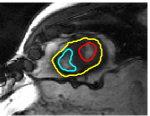

V-D Multiple Region Segmentation: Full Heart Segmentation

We now demonstrate our approach in performing challenging full heart segmentation: segmentation of the ventricles and epicardium all in one shot. Both the RV and epicardium are especially challenging as the contrast of the RV and background is subtle in comparison to the LV, and the myocardium wall near parts of the RV is very thin. We are not aware of another interactive method that is able to segment all structures, and so we compare to Medviso even though the method is not specifically tailored to the myocardium, but the method is generic and is able to propagate a segmentation. Further, Medviso does not segment multiple regions all at once and thus we perform separate segmentation of the LV, RV and epicardium. Since ground truth is not available for the outer wall of the myocardium in any standard dataset that we aware of, we show visual comparison.

Figure 10 shows the slice-wise results of our method and Medviso on a full 3D cardiac MRI sequence for a full cardiac cycle. Results indicate that our method is more accurate in capturing the shape of the ventricles and epicardium, and our method is especially more promising on the RV and epicardium. Figure 11 shows visualization of the results in 3D, and that our method more accurately resembles the structure of the heart.